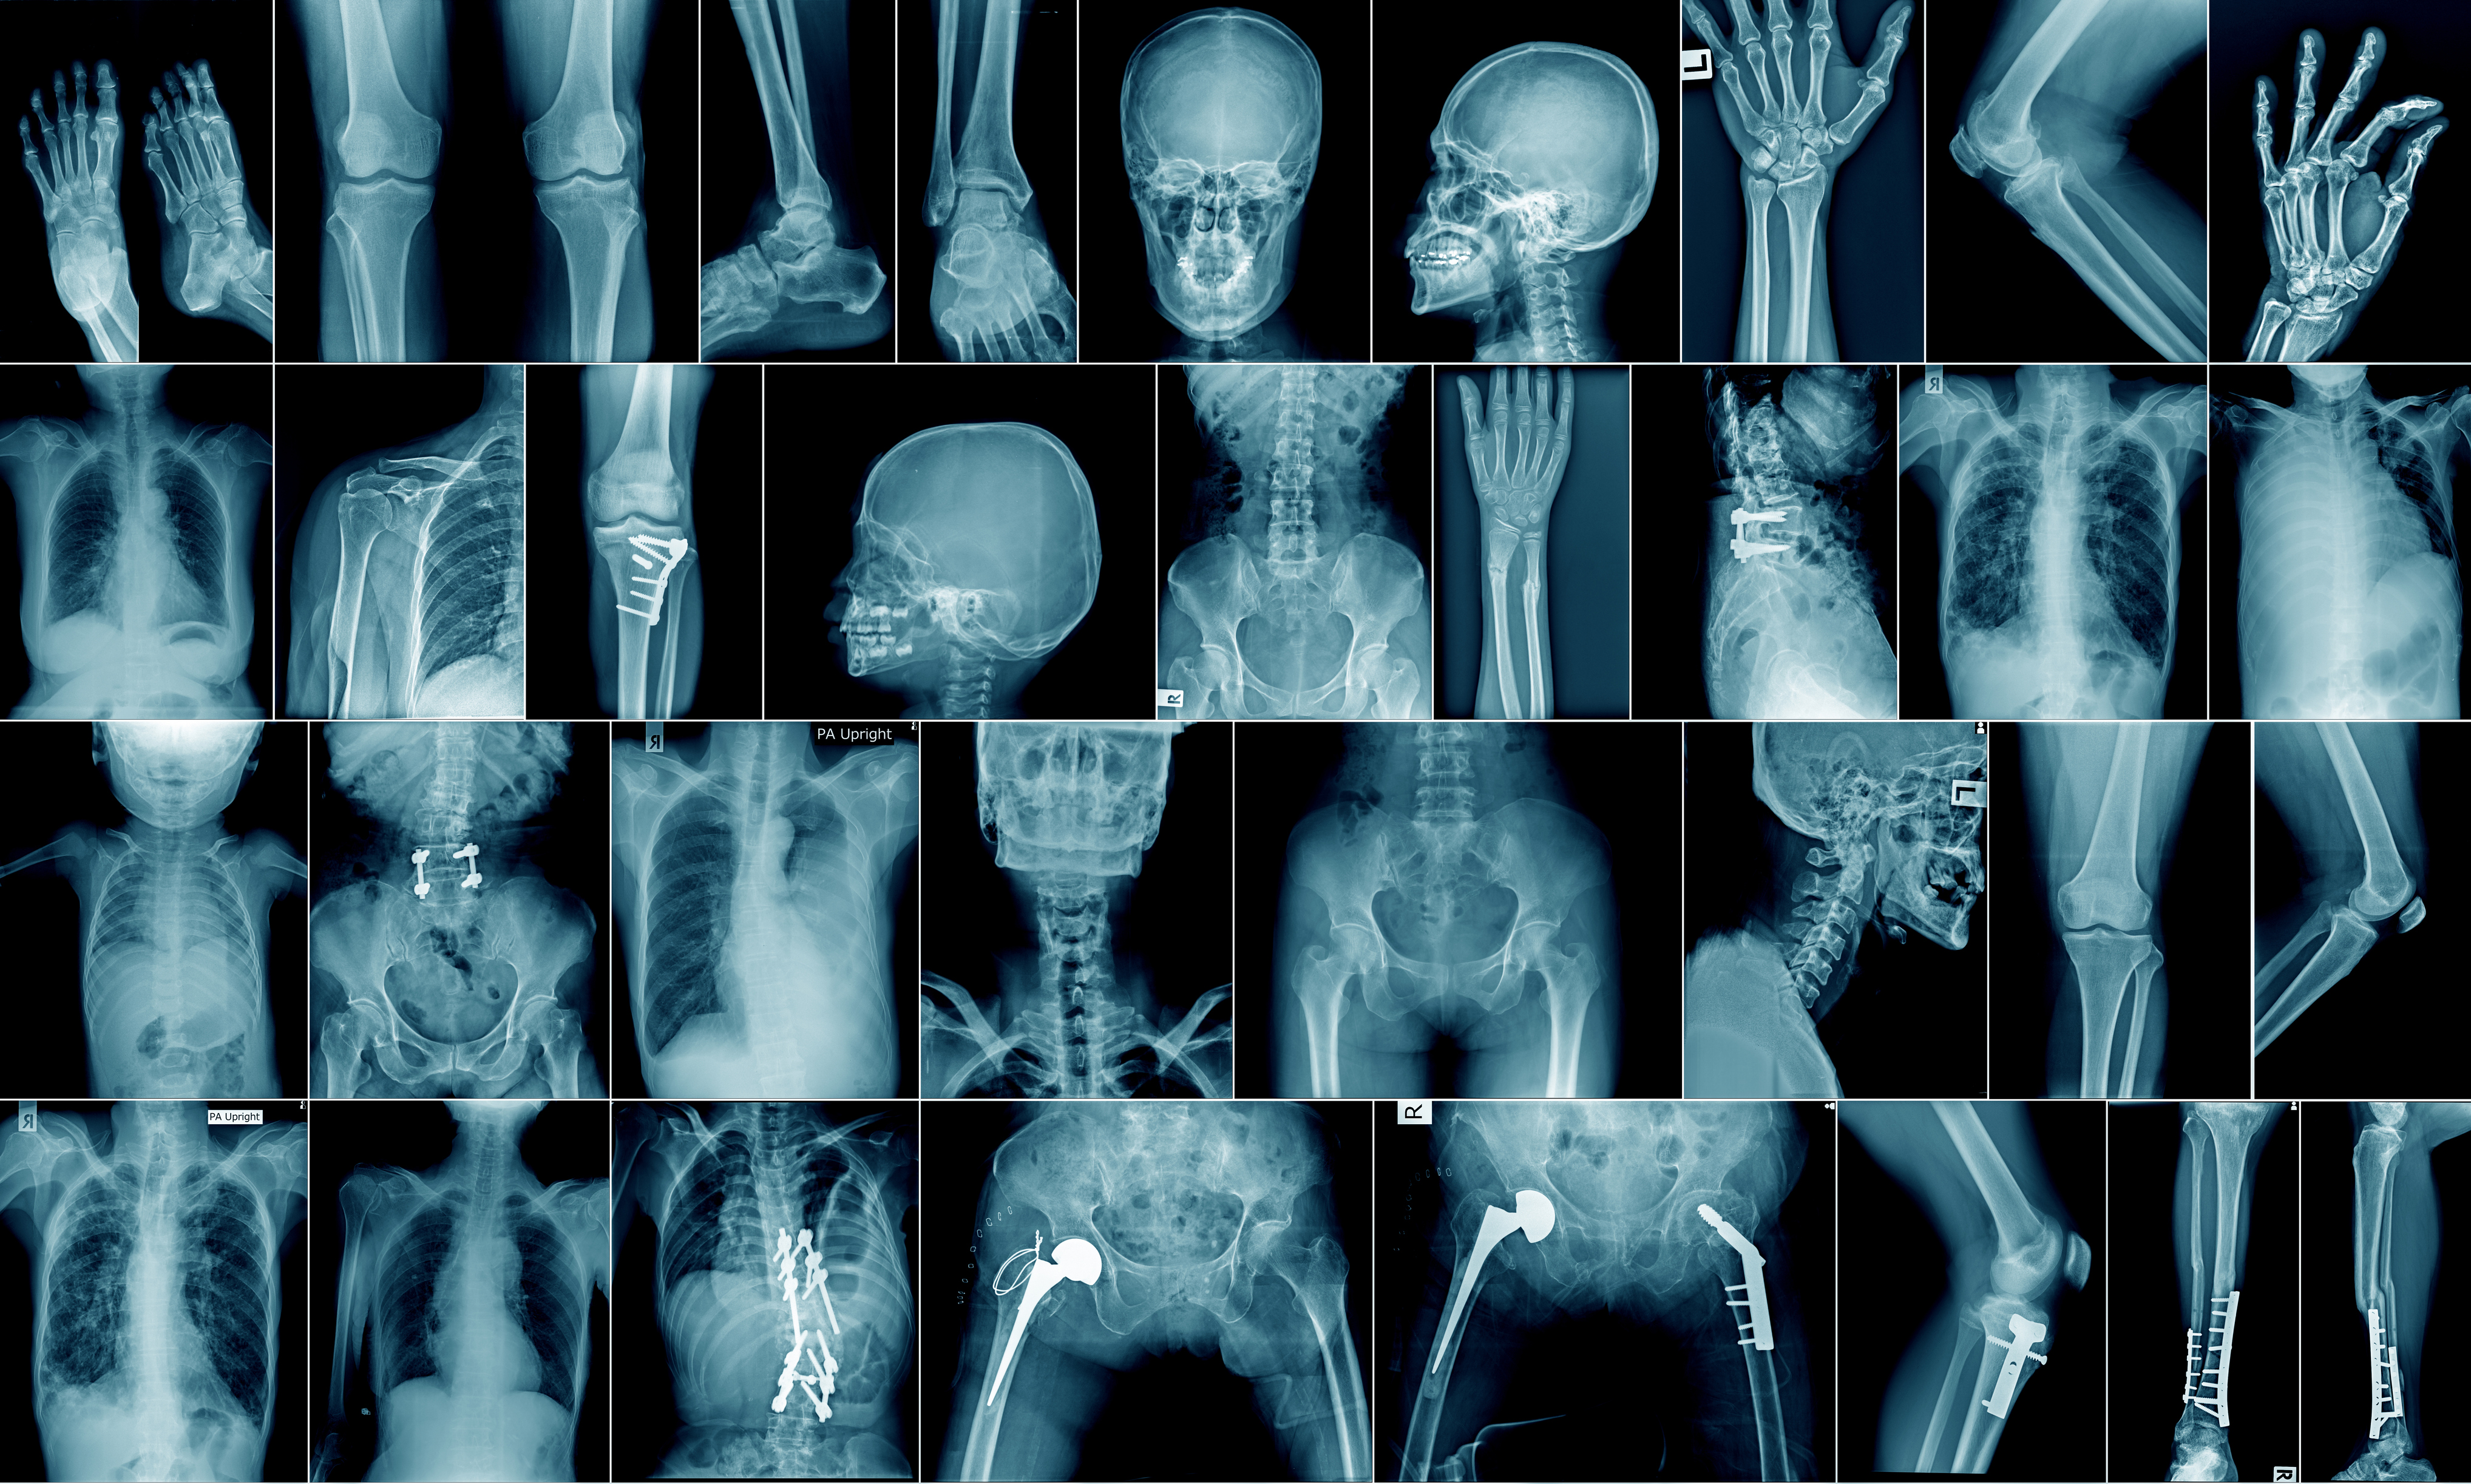

Spesialistutdanningen ved norske sykehus er i endring. Det er innført nye læringsmål for LIS-leger (1). Flere spesialiteter har fått radiologiske læringsmål inn i utdanningen, bl.a. indremedisin, akutt- og mottaksmedisin, øre-nese-hals-sykdommer, nevrologi og karkirurgi. Målene omfatter til dels avansert bildediagnostikk, bruk av ulike radiologiske modaliteter og både vaskulær og ikke-vaskulær intervensjon. For å bli øre-nese-hals-lege skal man f.eks. ikke bare «ha god kunnskap om og beherske bruk og tolkning av røntgen, CT og MR av hodet og halsområdet» (læringsmål ØNH-002) men også «selvstendig kunne utføre ultralyd og tolke røntgen, CT og MR av larynx og trachea» (læringsmål ØNH-031). For flere spesialiteter vil de radiologiske læringsmålene gi merarbeid, stjele tid fra deres tradisjonelle oppgaver og sannsynligvis forsinke utdanningsløpet.